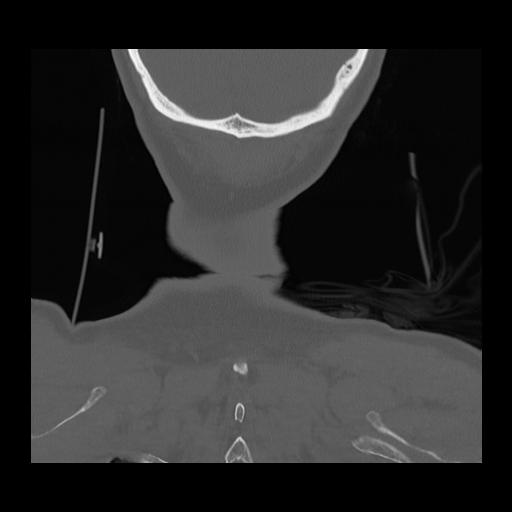

16 HUESO,,Coronal,2.000,HUESO,Coronal,